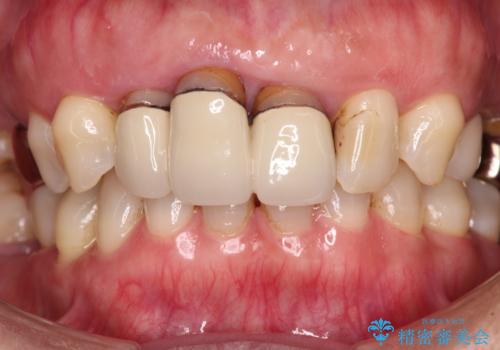

- 20年以上前に装着した前歯のメタルセラミックが不自然であることを気にして来院された患者様です。

歯肉の位置が変わり、変色した歯根が露出しているため、金属の土台をファイバーコアに交換した上で、オールセラミッククラウンにて補綴することとしました。

歯肉の位置は変更できないため、露出している歯根をクラウンで覆い隠すと歯が長く見えることを事前にお伝えしておりました。